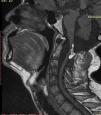

Intradural spinal lipomas with intracranial extension are very rare and are typically diagnosed in childhood. Radical surgical excision usually causes a high rate of morbidity because of the firm adherence between the lipoma and neural tissues. In this report, we present a case of craniocervical intradural intramedullary lipoma in an adult patient. The patient underwent surgery with excision of the mass, leaving a sheet of lipoma on the tumor bed.